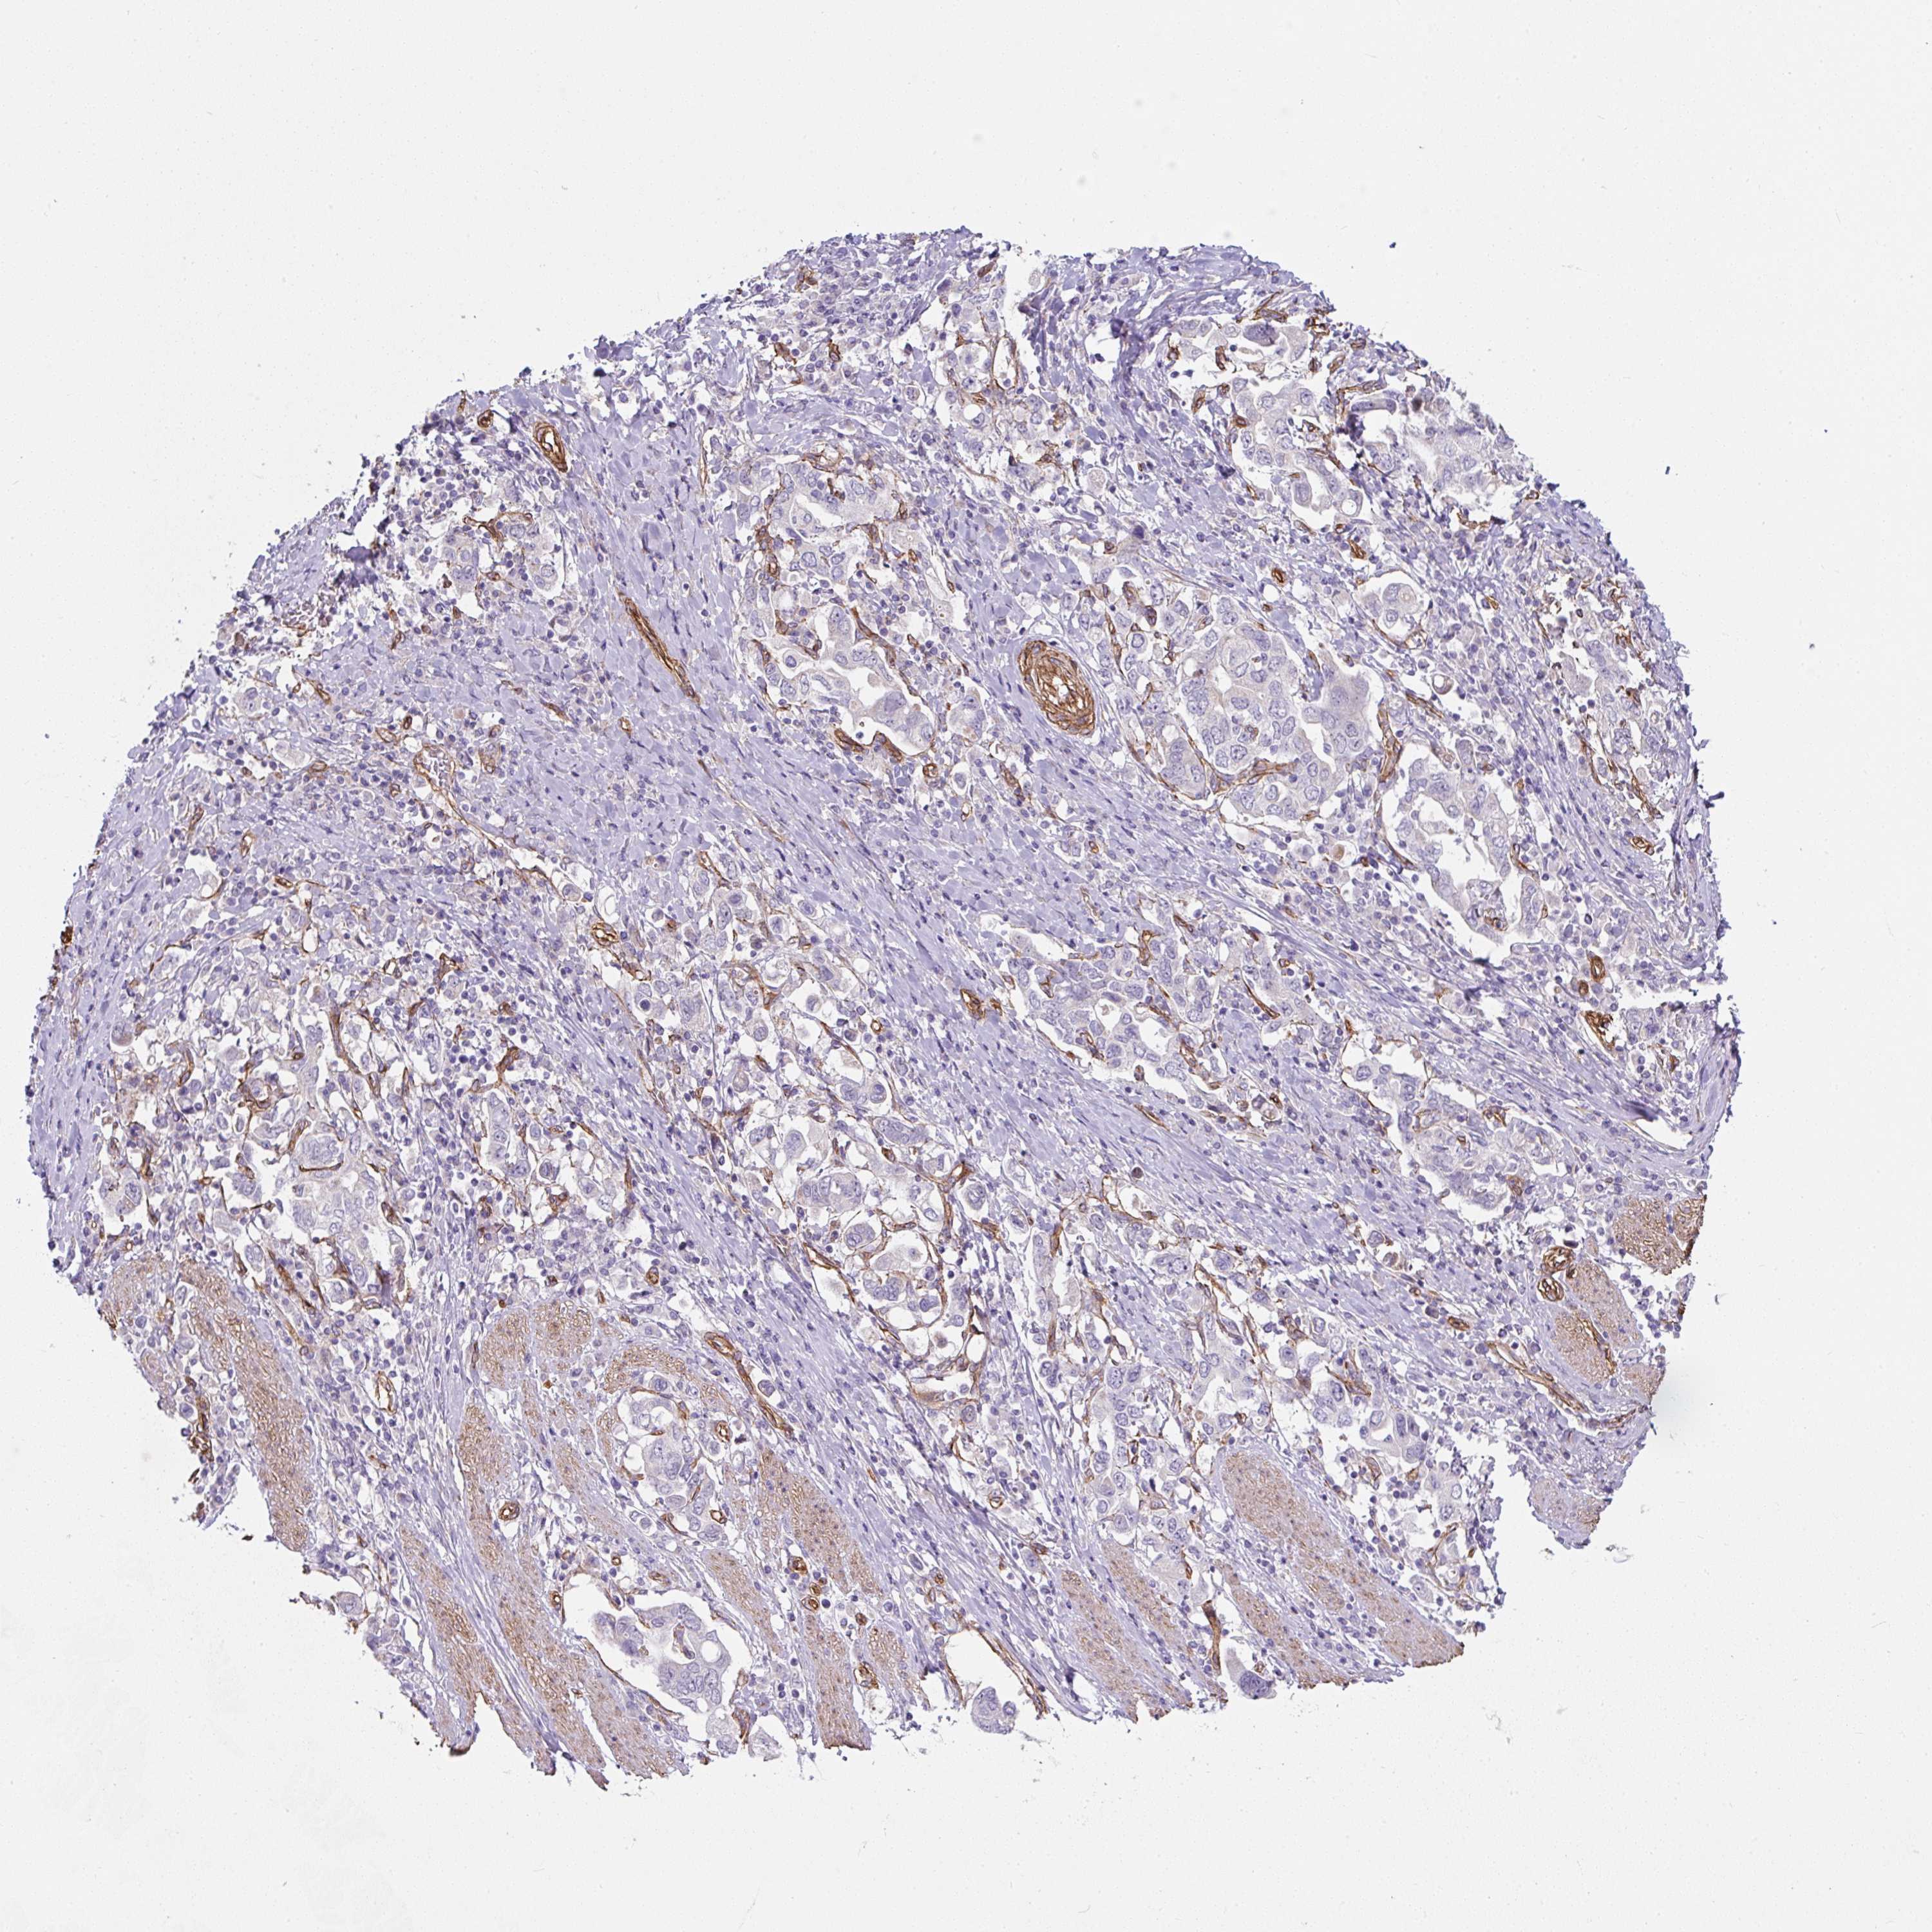

STOMACH CANCER - Protein expressioni

A mouse-over function shows sample information and annotation data. Click on an image to view it in a full screen mode. Samples can be filtered based on level of antibody staining by selecting one or several of the following categories: high, medium, low and not detected. The assay and annotation is described here.

Note that samples used for immunohistochemistry by the Human Protein Atlas do not correspond to samples in the TCGA dataset.

Antibody stainingi

Antibody staining in the annotated cell types in the current human tissue is reported as not detected, low, medium, or high, based on conventional immunohistochemistry profiling in selected tissues. This score is based on the combination of the staining intensity and fraction of stained cells.

Each image is clickable and will lead to virtual microscopy that enables deeper exploration of all samples and also displays staining intensity scores, fraction scores and subcellular localization as well as patient and tissue information for each sample.

Antibody HPA053749

Staining

High

Medium

Low

Not detected

Intensity

Strong

Moderate

Weak

Negative

Quantity

>75%

75%-25%

<25%

None

Location

Nuclear

Cytoplasmic/membranous

Cytoplasmic/membranous,nuclear

Adenocarcinoma, NOS